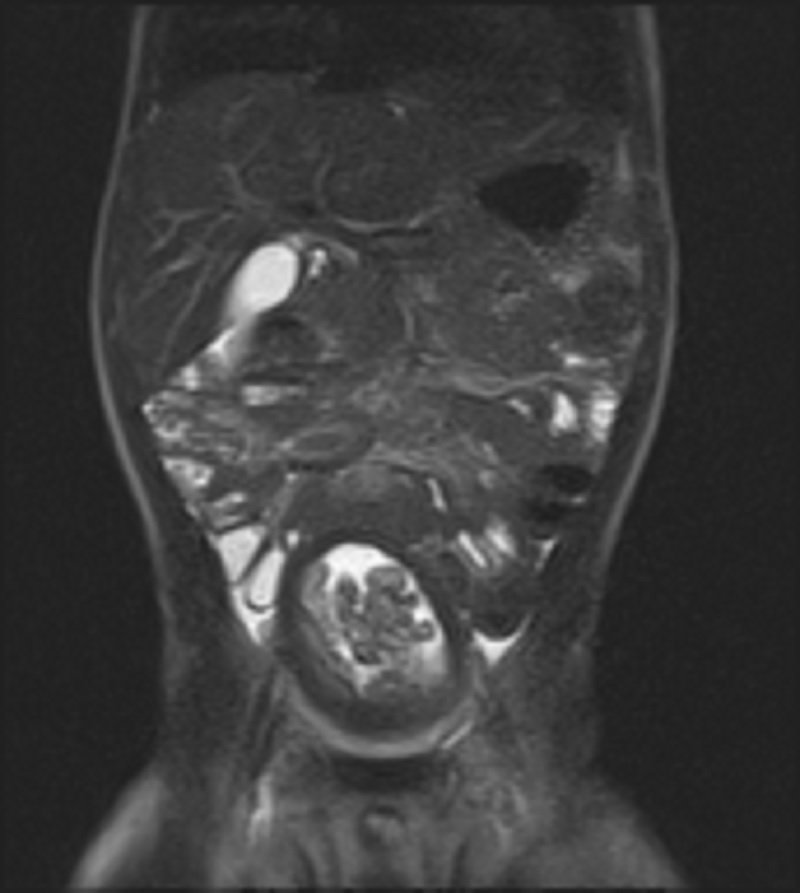

-year-old male presents with hematuria. An MRI scan was performed. Axial and coronal T2-weighted images are shown.

There is a polypoid mass in the bladder. The grape-like appearance is characteristic of the botryoid type of rhabdomyosarcoma. Rhabdomyosarcomas are the most common malignant bladder masses in the pediatric population.

Paragangliomas of the bladder may have a similar appearance with a macrolobulated appearance and T2-hyperintense signal, but they are more often seen in patients ages 30 to 60. Hemangiomas are often seen in the setting of other vascular malformations and are similar in appearance to hemangiomas seen elsewhere. Cystitis glandularis may present as nodules on a background of diffuse bladder wall thickening. Bladder neurofibromas are rare and may demonstrate a target appearance on T2-weighted imaging, with central low signal and peripheral high signal.